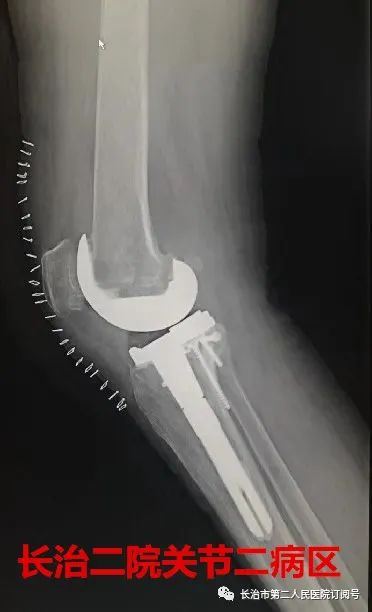

走路 在常人来看 是件多么轻松的事情 可对于李老太来说 近日,长治二院骨科关节二病区来了一位严重类风湿性关节炎患者,疾病困扰了她13年,日常行走已经很困难了。 长治二院骨科关节二病区 雷晓宇医师团队妙手回春 完美实施双膝关节置换术 随即轻松行走! 对李老太来说 走路成为了一种享受 今年69岁的李老太在13年前双膝先后出现疼痛无力的症状,但随着年龄的增长病情逐年加重,双腿关节等处都严重变形。双膝并拢时成“顺风腿”畸形,行走也变得相当困难,行各种保守治疗方案效果差,双膝疼痛行走受限,严重影响了日常生活。 图为:术前MRI及CT 图为:术后X片 据李老太的主管医生朱彦伟副主任医师介绍“重度外翻性膝行膝关节置换,由于其软组织不平衡及存在严重的骨缺损,手术难度极高,对于关节外科医师而言,绝对是充满挑战性事件! 入院后,骨科关节二病区雷晓宇医师团队术前进行仔细的手术规划,充分的术前准备,为李老太制定个性化治疗方案,对存在不同严重畸形的双膝分别行人工膝关节表面置换术。术后第二天就可以在助行器的保护下下床行走。经过精心的康复治疗,目前李老太的行走步态正常,生活质量明显提高。科室医护人员对李老太住院期间的精心治疗和护理,更是让老人及家属感受到了长治二院医护团队的专业素养和暖心服务。 对于像李老太这样的类风湿性关节炎患者,长治二院骨科关节二病区雷晓宇主任特别提醒:一旦出现疼痛、关节畸形、保守治疗无效后,应尽早行膝关节置换。 朱彦伟 关节二病区副主任医师 朱彦伟医师:周四全天门诊 电话:158 3551 0903 ■ 直通大医院丨9月18日长治二院关节外科一病区主任张鹏为您讲解《股骨头坏死的预防与诊治》 ■ 皮肤病患者的福音——又一“名医工作室”落户长治二院!!! ■ 长治二院特邀北京大学第一医院皮肤科教授陈喜雪来院指导讲学 供 稿丨朱彦伟 视 频 | 朱彦伟 编 辑丨张静晗 审 核丨雷 赫